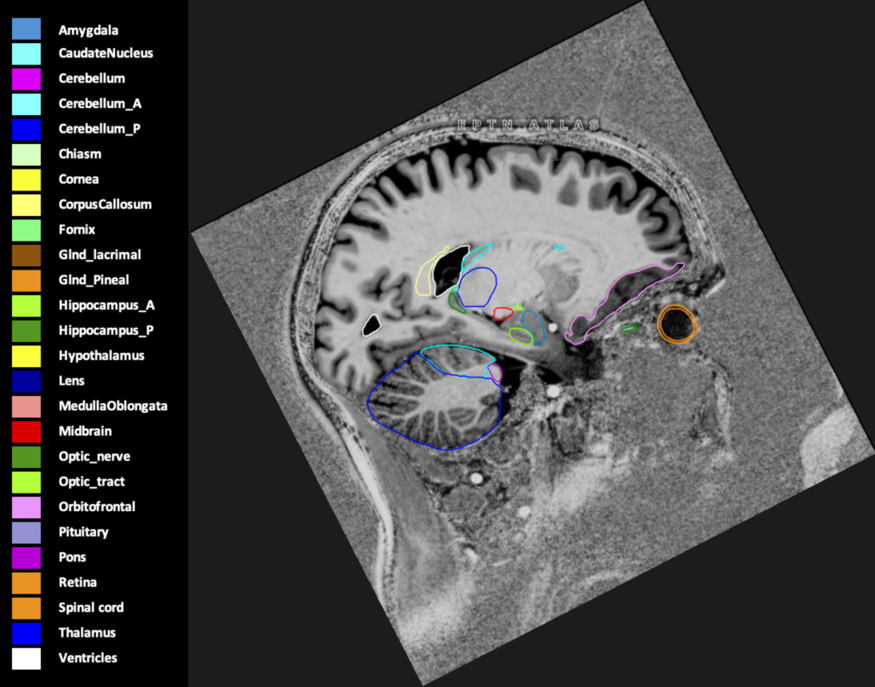

Eekers et al. have published an international neurological atlas for contouring of organs at risk in consensus with the European Particle Therapy Network (EPTN) in 2018 and an update in 2021. The purpose of this consensus atlas is to decrease inter- and intra-observer variability in delineating OARs relevant for neuro-oncology.

Included are all OARs known to be relevant for radiation-induced toxicity in neuro-oncology: brain, brainstem (midbrain, pons, medulla oblongata), chiasm, cerebellum (anterior & posterior), cochlea, cornea, hippocampus (anterior & posterior), hypothalamus, lens, lacrimal gland, optic nerve, pituitary, skin, and vestibular & semicircular canals. To further facilitate research on cognition, vision and radiological changes after irradiation of the brain, potential clinically-relevant OARs are included: amygdala, caudate nucleus, cerebellum (anterior & posterior), corpus callosum, fornix, macula, optic tract, orbitofrontal cortex, periventricular space (PVS), pineal gland, and thalamus.

Three-dimensional delineation of the 25 consensus OARs for neuro-oncology are shown on CT (WW/WL 120/40, 3000/600), 3T MR images, (T1Gd, T2FLAIR 1mm) and 7T MR (MP2RAGE 0.7 mm). All are presented in transversal, sagittal and coronal view.